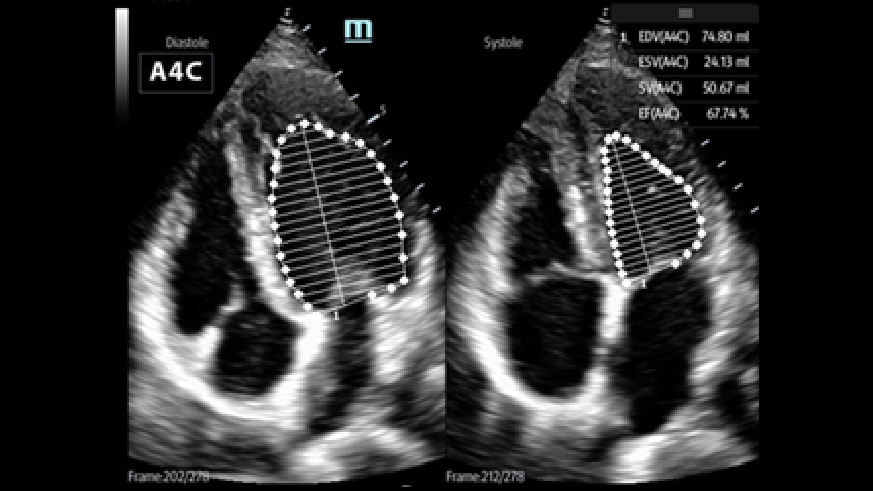

Toepassing voor kritieke zorg

Met uitzonderlijke cardiale beeldvormingsprestaties en geavanceerde analysetools biedt ME een combinatie van kwaliteit, effici?ntie en draagbaarheid voor kritieke zorgscenario's.

2Smart VTI

Automatische meting van de VTI (Velocity Time Integral ) en CO (Cardiac Output), voor een snelle beoordeling van de hartfunctie. Zoek automatisch het kleurvlak en de PW-samplelijn in realtime. Een grafiek met parametertrends over CO, SV en VTI om de besluitvorming te ondersteunen.